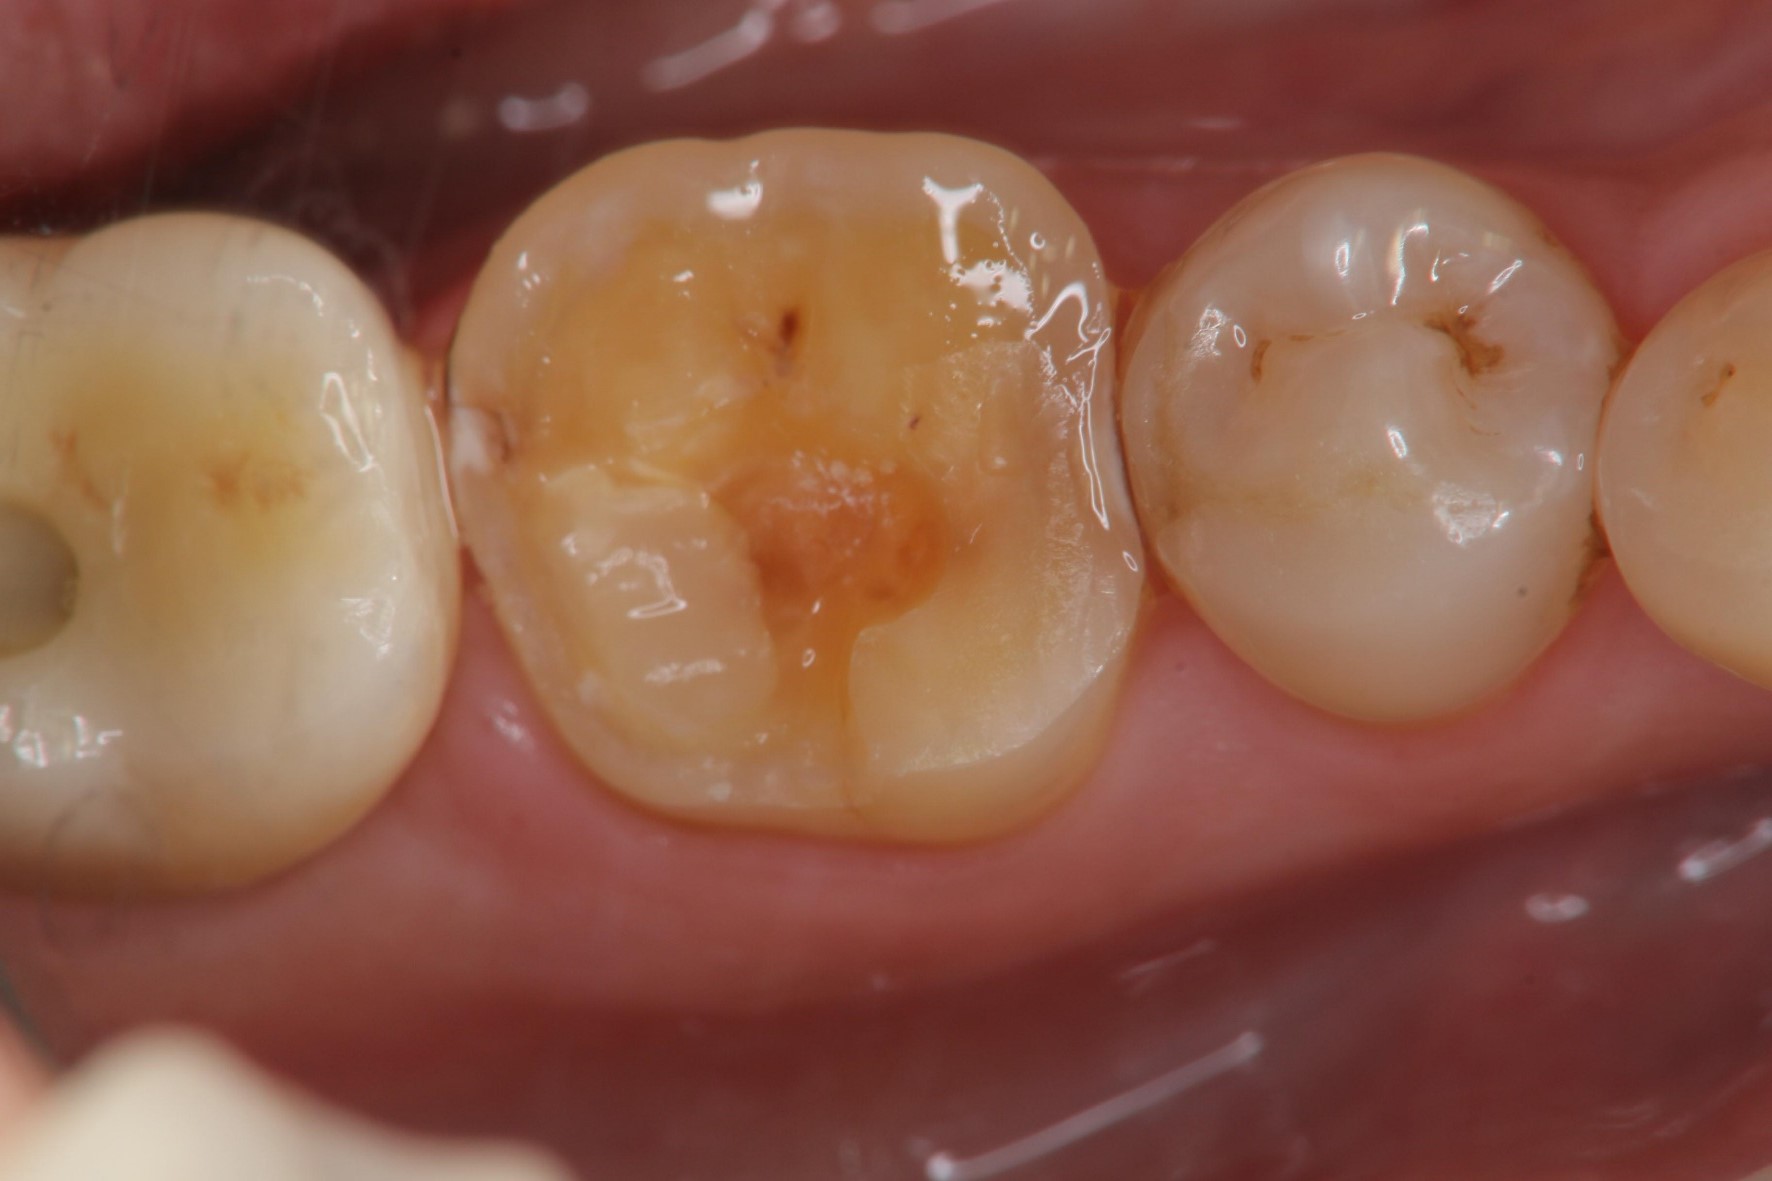

冠塊體體製備